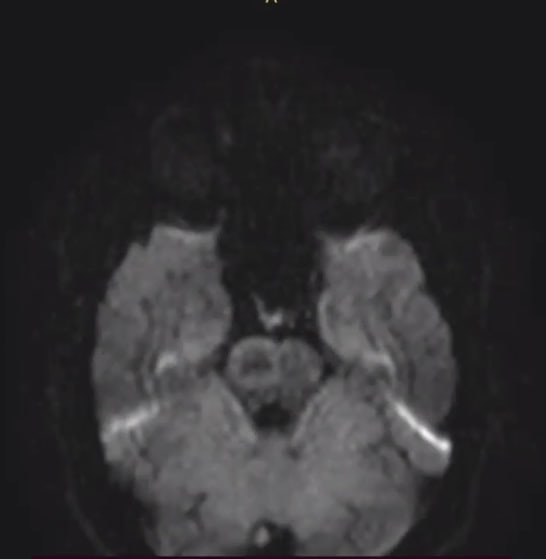

Сходил в центр РС, снова на МРТ (прошло почти 4 месяца).

Был сегодня на МРТ, с марта динамики нет.

Опытным анонимам вопрос, что хуже/опаснее всего в моем заключении МРТ?